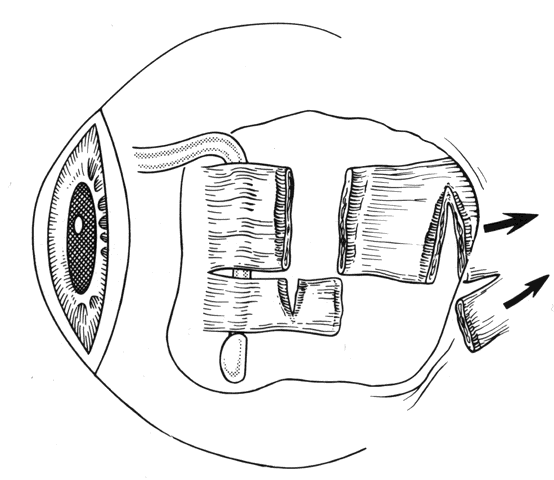

Reintervention to correct strabismus is indicated if a technical problem occurred immediately after the initial procedure. A muscle that has become disinserted or is “lost” postoperatively requires immediate exploration and correction of the problem (Figs. 2 and 3). A similar situation may occur when a previously operated muscle retracts ("slips") inside the muscle capsule (Fig. 4). The slipped muscle will appear paretic, and early surgical intervention should be considered. The clinical pictures of these technical failures are very similar. There is poor function of the affected rectus muscle, and the induced strabismus will be noncomitant. Operations may be performed on the incorrect eye muscles or eye (Fig. 5). If this occurs, reoperation should not be delayed.

Fig. 3. This diagram demonstrates the findings of surgical exploration of the patient in Figure 2.

Fig. 4. Failure to incorporate a portion or the entire tendon of the muscle when sutures are placed near the insertion can permit a portion or all of the muscle to slip posteriorly and produce an exaggerated recession effect. On exploration, the muscle capsule will be present but the tendon will be retracted within the muscle capsule.